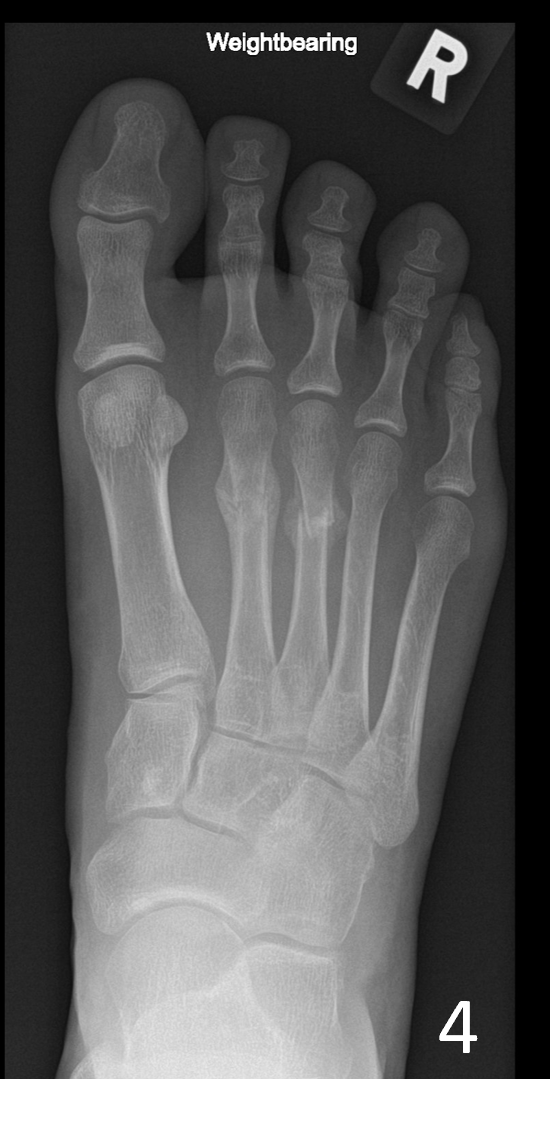

A 29-year-old female, presented with pain and a lump on the dorsum of her right foot. She was training for a 10km run and had been struggling with running over a 6-week period. No history of trauma or erythema to the skin. The clinical suspicion was a ganglion, and the patient was referred for an ultrasound scan for further assessment.

On the dorsum of the foot, ultrasound demonstrated marked cortical irregularity and callus formation around the third metatarsal shaft accounting for the palpable ‘lump’ with surrounding soft tissue swelling (Figure 1). On power Doppler, there was marked peripheral vascularity in the surrounding soft tissues (Figure 2). Incidentally, there was also cortical irregularity and callus formation around the second metatarsal shaft although the patient was not particularly tender here whilst scanning (Figure 3). The cortical irregularity in the second metatarsal shaft was minimal when compared to the third metatarsal and there was no neovascularisation on power Doppler indicating this was an older/mature injury.

Ultrasound appearances in keeping with acute and chronic stress fractures. A radiograph confirmed old and new callus formation (Figure 4). Conservative treatment comprised rest and analgesia. Surgery is generally reserved for stress fractures that do not heal.